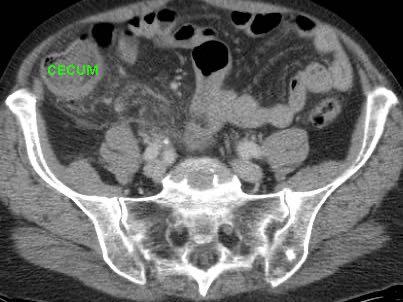

Ở người phụ nữ 56 tuổi này với CRP 180, siêu âm phát hiện dịch trong phúc mạc đục (*) và có thể thấy ruột thừa viêm với sỏi phân (mũi tên).

CT xác nhận hai sỏi phân ở hố chậu phải với hình ảnh khí bất thường, nghi ngờ viêm ruột thừa thủng.

Chọc hút dưới hướng dẫn siêu âm xác nhận dịch mủ.

Phẫu thuật cấp cứu phát hiện viêm ruột thừa thủng với nhiễm bẩn mủ bốn góc phần tư ổ bụng.